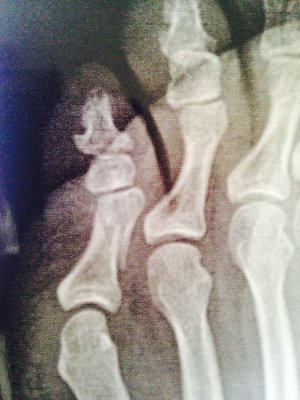

Здравствуйте! 28 декабря ударилась об угол кровати. Рентген показал косой перелом дистального отдела проксимальной фаланги 5 пальца стопы. Врач сказал, что смещение минимальное. Предложил гипсовую лангетку, но я отказалась, тогда дал жёсткую штучку и сказал обрезать по форме стопы, привязать и ходить на пятке. Прошло больше 3 недель, сделала контрольный снимок (прилагаю), врач утверждает, что всё хорошо, процесс срастания идёт, сказал надо ещё 10 дней ходить с фиксацией.

1. Действительно ли по снимкам нет смещения?

2.я, сравнивая первые снимки и после 3 недель не вижу никакого прогресса в сращении..Он есть?